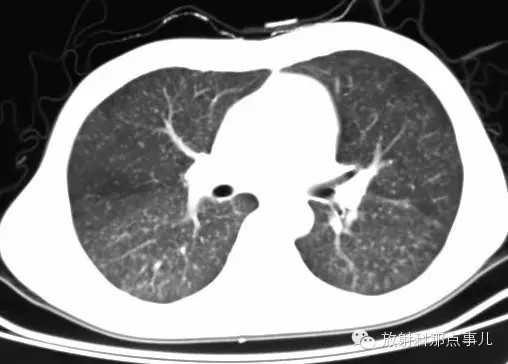

影像表现

1.胸片示双肺网状纹理,弥漫分布粟粒样病灶,由上至下病灶逐渐增多。

2.CT示双肺网状纹理,弥漫分布粟粒样病灶;HRCT示左肺上叶舌段肺气囊。